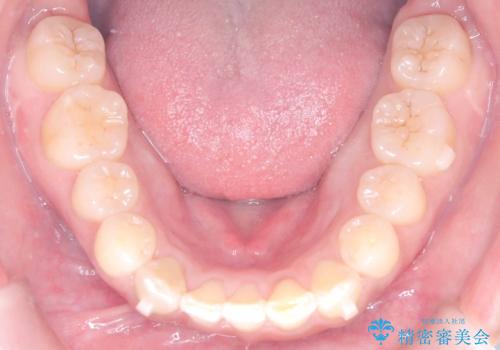

- 「歯の捻じれとがたつき」を主訴に来院された患者様です。

軽度な捻転と叢生だったため、インビザラインのモデレートで治療を行いわずか半年で治療を終える事が出来ました!